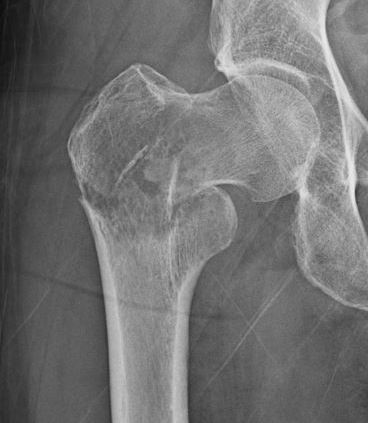

Femoral Neck pathological fracture / Major bone loss

Issues

- fracture unlikely to heal

- hemi versus THA

- long versus short stems

Femoral neck stabilization

- sufficient bone for fixation?

- determine if lesions further down femur (xray entire femur)

- consider augmentation with PMMA / cement

Plate versus IM nail